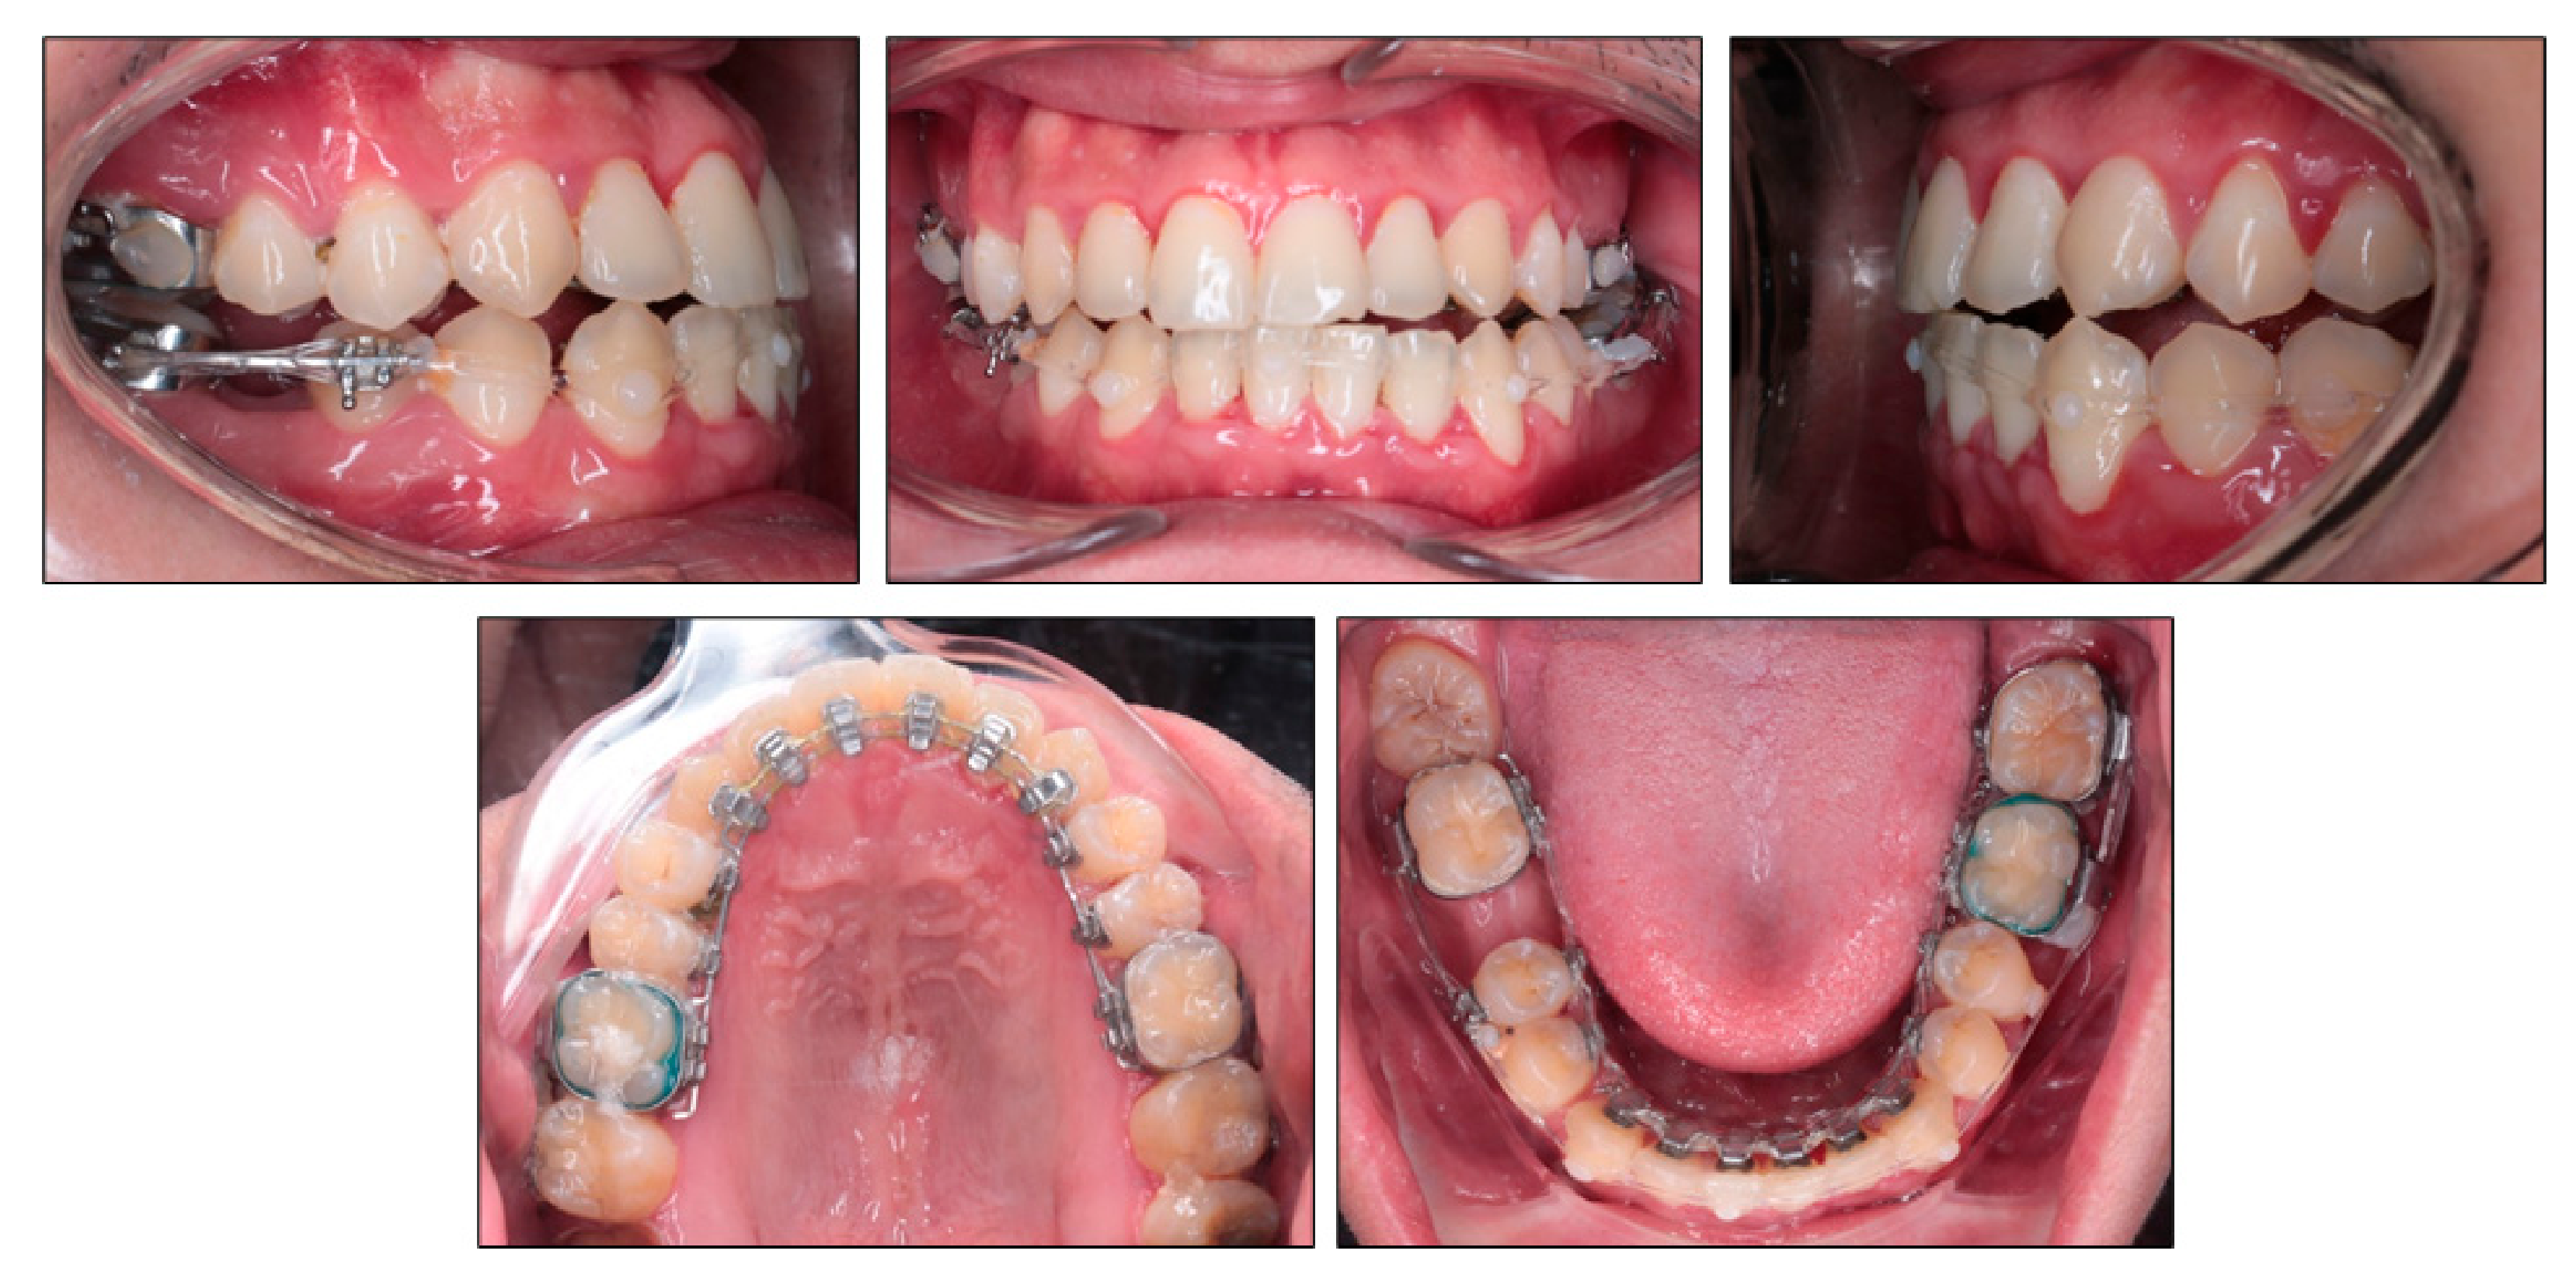

After seven months of treatment, the upper archwire was 0.018 × 0.018 in nickel titanium archwire and the lower archwire was 0.018 × 0.018 in stainless steel archwire. The space closure stage was initiated with elastic chains from mandibular right second molar to mandibular left third molar both lingually and labially to prevent rotation and transverse bowing effect (Figure 4). The right third molar tube was banded labially for easier handling. Clear composite buttons were bonded on the labial surface of mandibular canines for applying elastic chains. The labial bracket was bonded on the lower right second premolar and segmental archwire was placed between mandibular right second premolar and second molar to avoid tipping of these teeth into extraction space. On the initial space closure stage, the mandibular right third molar was not banded yet to allow spontaneous mesializing.

Figure 4.

Space closure with labial and lingual elastic chains in the lower arch.